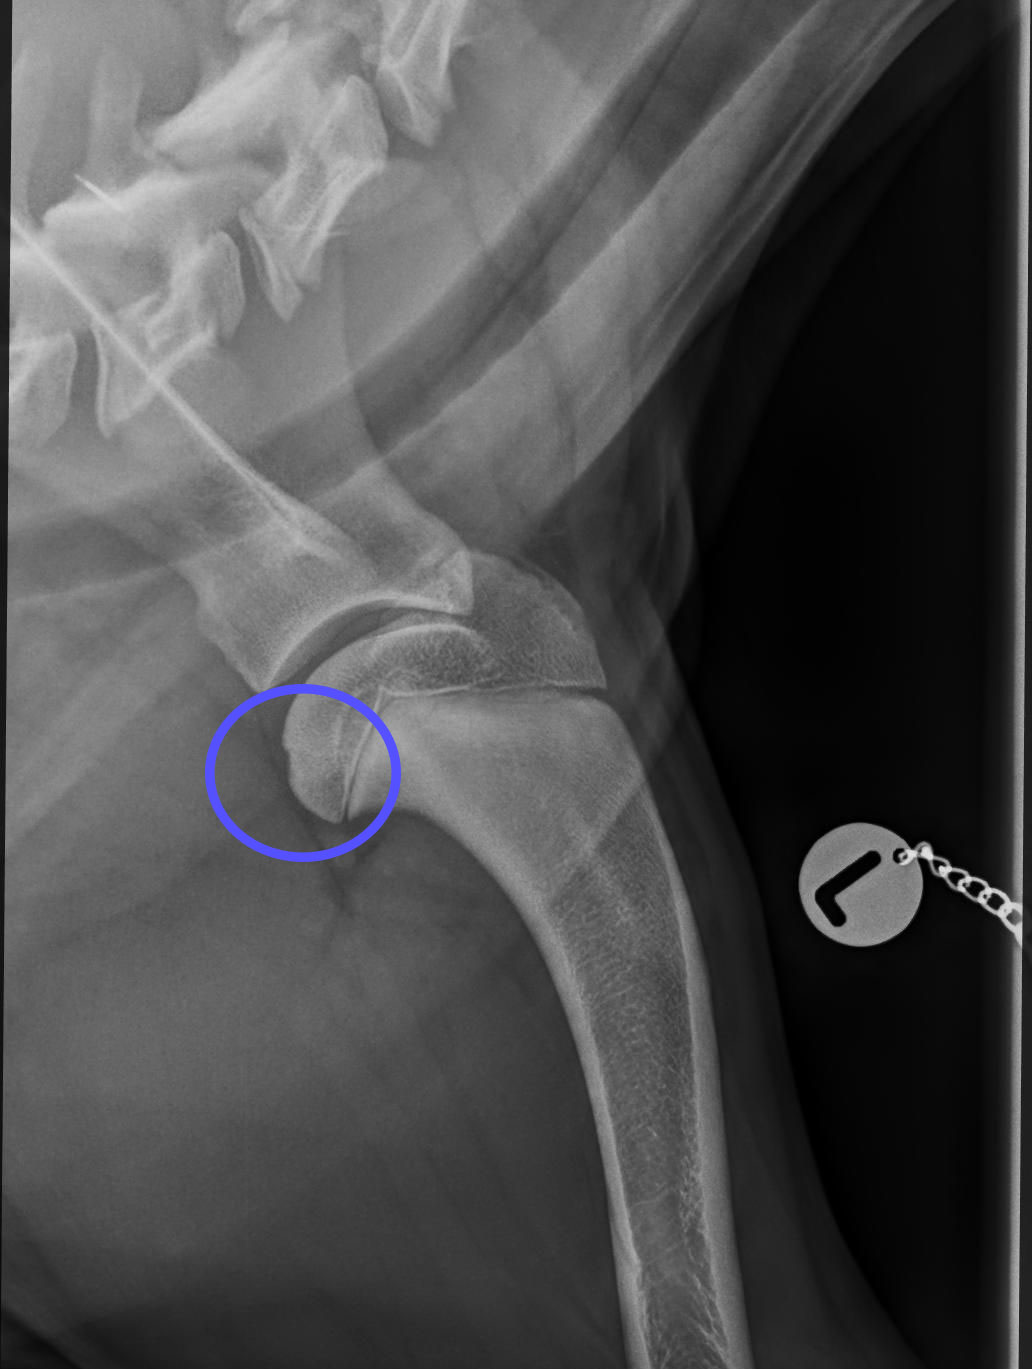

HD Grad A

HD Grad E